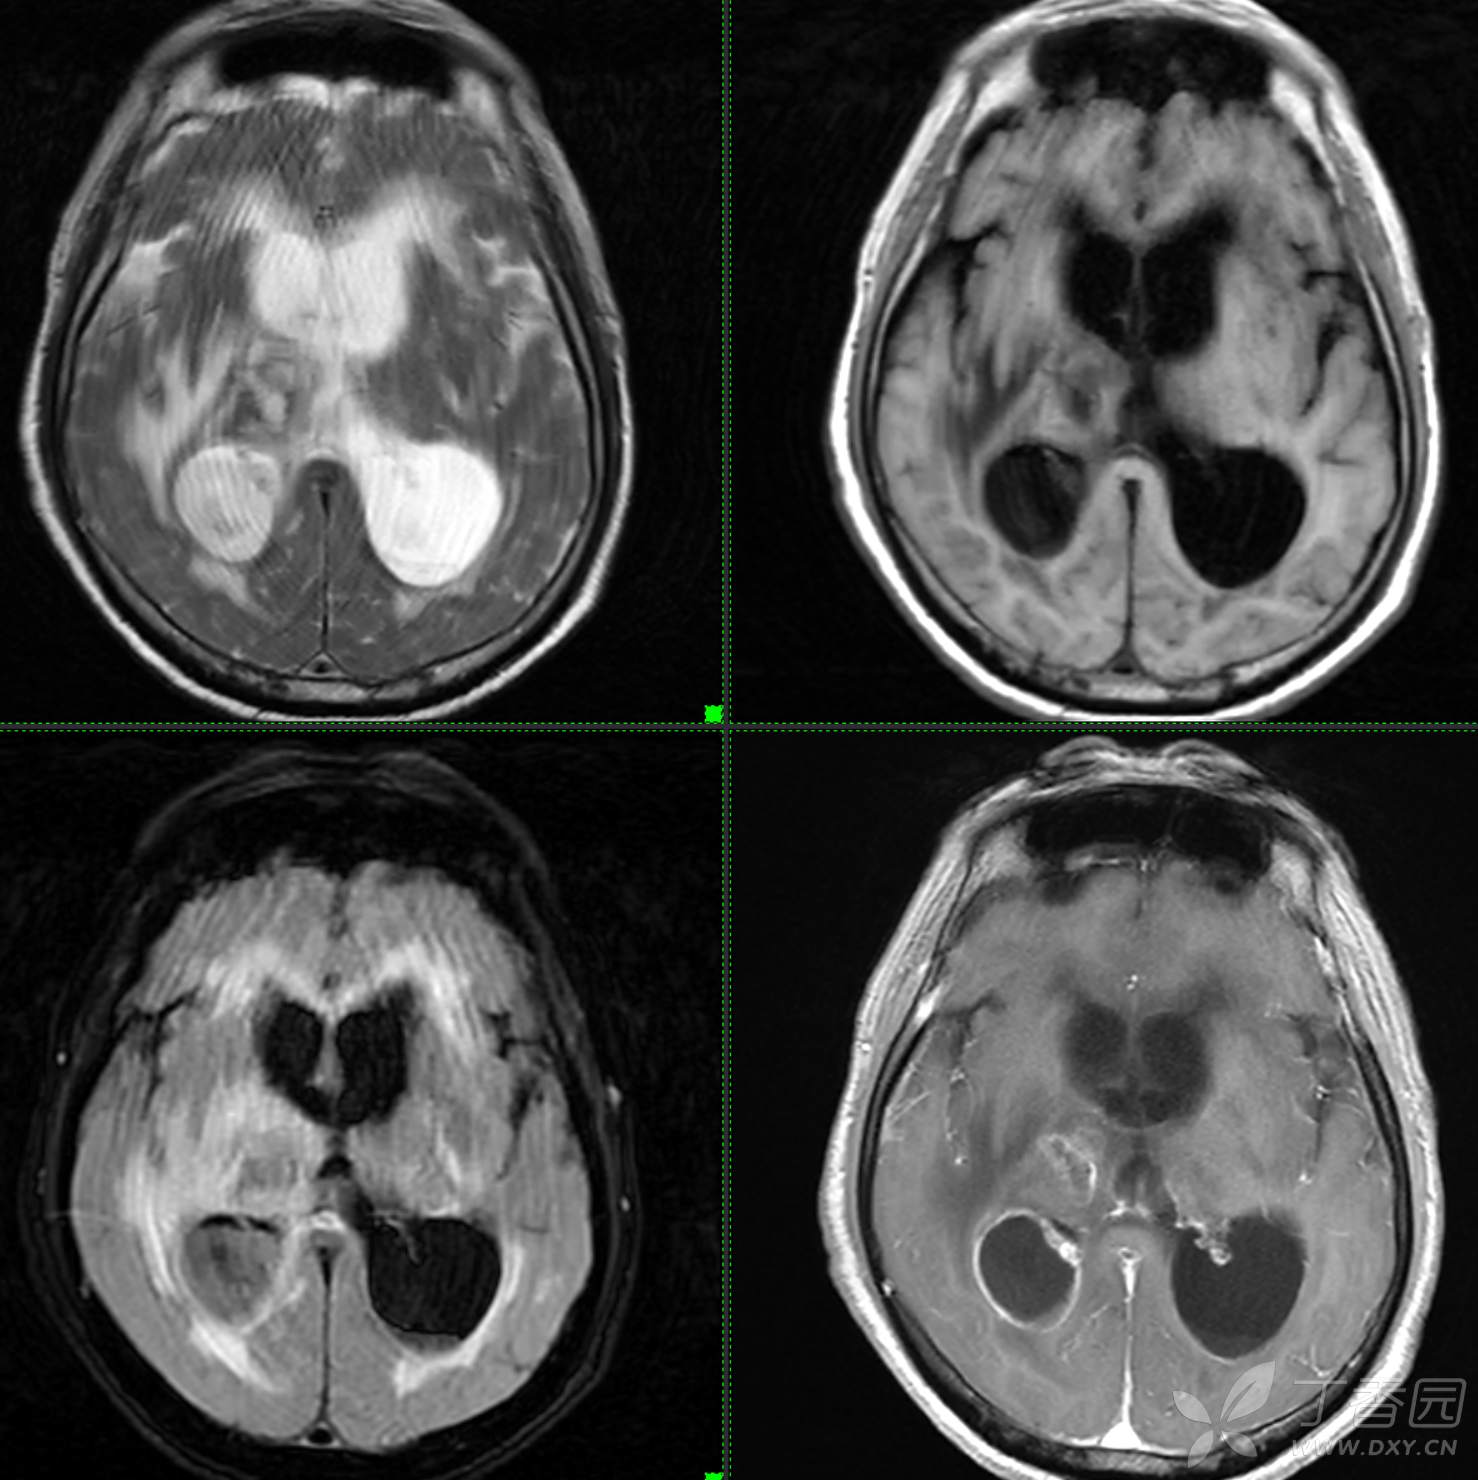

头颈组9:简单分析,诊断不难。

主诉: 【头晕乏力数周,发热1周】

现病史: 患者3周前无明显诱因下出现头晕,无头痛,伴视物模糊,肢体乏力,走路步态不 稳,无意识不清,对答切题,当地医院查血常规示:中性粒细胞分类:77.7%.淋巴细胞分类:15.6%,中性性粒细胞分类:7.1*10^9/L.葡萄糖:22.35mmol/,头颅平扫示:右侧丘脑饱满,密度减低伴低密度灶,占位不排除,两侧半卵圆区、额叶低密度灶,以“1.糖尿病酮症酸中毒,2.颅内占位性病变”收入住院治疗,1周前住院期间出现发热,先后予抗感染,控制血糖等对症支持治疗,2天前无明显诱因下再次出现发热,伴血糖升高,自测体温40℃,血糖20mmol儿,伴气促无胸闷,袖志模糊,反应迟钝,无畏寒寒战,无腹痛腹泻等不适,昨日送至我院就诊